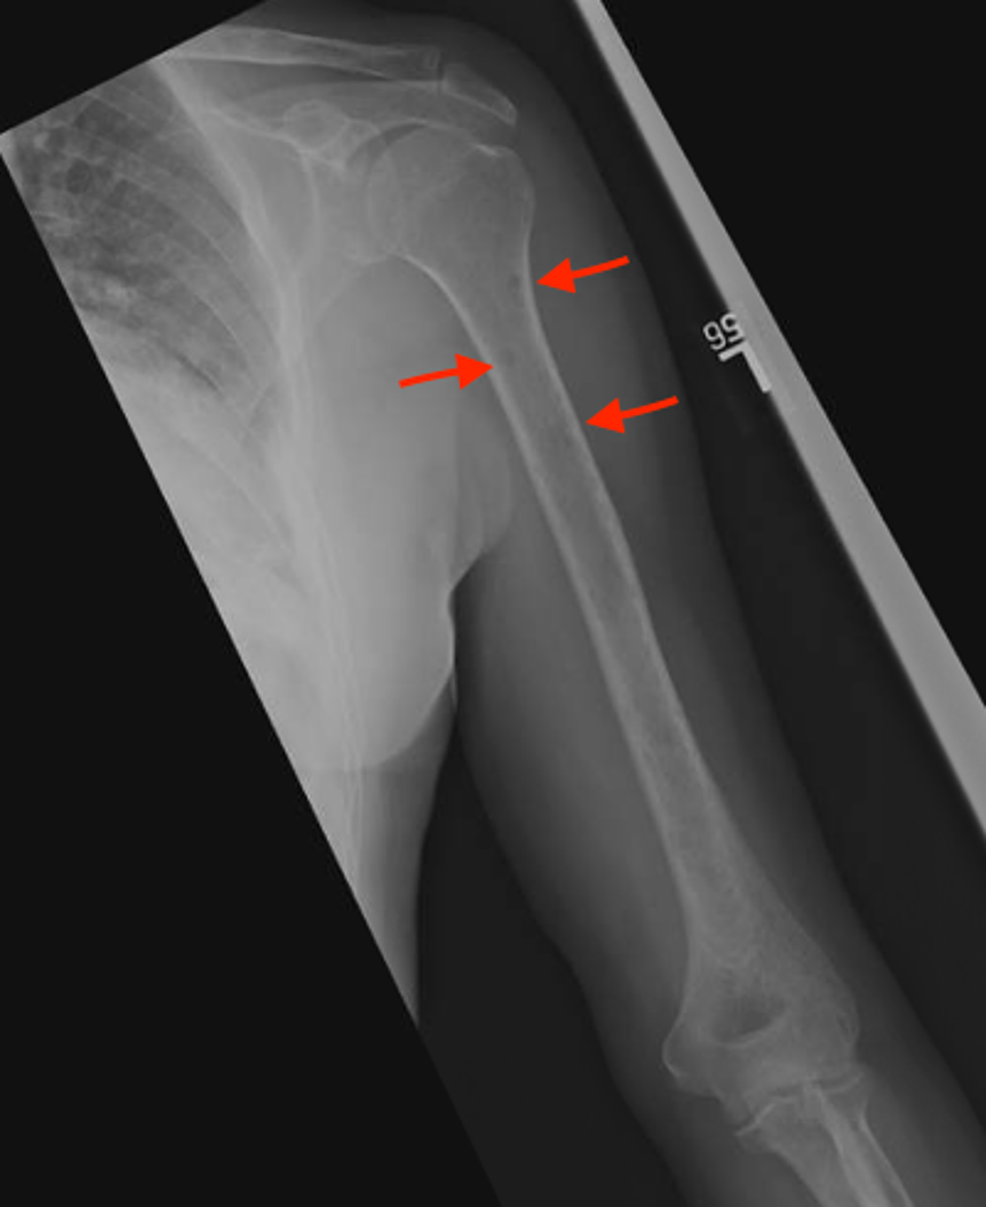

View Multiple Myeloma Bone Lesions Pictures. Multiple myeloma is a type of blood cancer. Myeloma bone disease can cause the bones to become thinner and weaker (osteoporosis), and it can make holes appear in the bone (lytic lesions).

Osteolytic lesions result from increased bone resorption due to osteoclast stimulation and decreased bone formation due to. Multiple myeloma isn't the only form of cancer that can multiple myeloma research foundation: Multiple myeloma (kahler's disease) is a malignant plasma cell dyscrasia characterized by uncontrolled proliferation and the diffuse infiltration of monoclonal plasma cells in the bone marrow. Multiple myeloma is a rare condition that causes cancerous plasma cells to be produced, multiply and build up in the bone marrow.